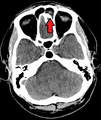

| Left-sided maxillary sinusitis marked by an arrow. Note the lack of the air transparency indicating fluid in contrast to the other side. | |